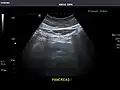

Pancreas -